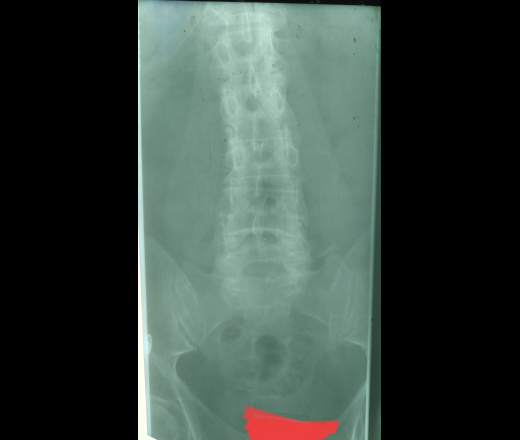

Коллеги, здравствуйте! Мужчина, 60 лет. Жалобы на боли в спине. За травмы данных нет.

1) Что это могут быть за линейные участки просветления? Аномальные сочленения? Spina bifida?

2) Что это за зона кистовидной перестройки может быть в крестце на боковом снимке? Или это скиалогия?

Антелистез L4. Кружки это скиалогия.

+1. Есть причина появления болей